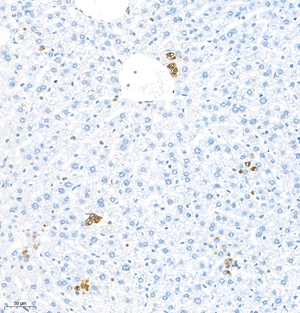

| IHC analysis of MPO (GB11224). Sample: Mouse bone (Paraffin), 4% PFA (G1101) 12-24h. Antigen retrieval: Citrate buffer (pH 6.0) (G1201),98°C,20 min. Blocking buffer: 3% BSA in PBS (GC305010), RT, 30min. Primary antibody: 1: 800, 4°C overnight. Secondary antibody: HRP Goat Anti-Rabbit lgG (GB23303), 1: 200 RT 1h. |